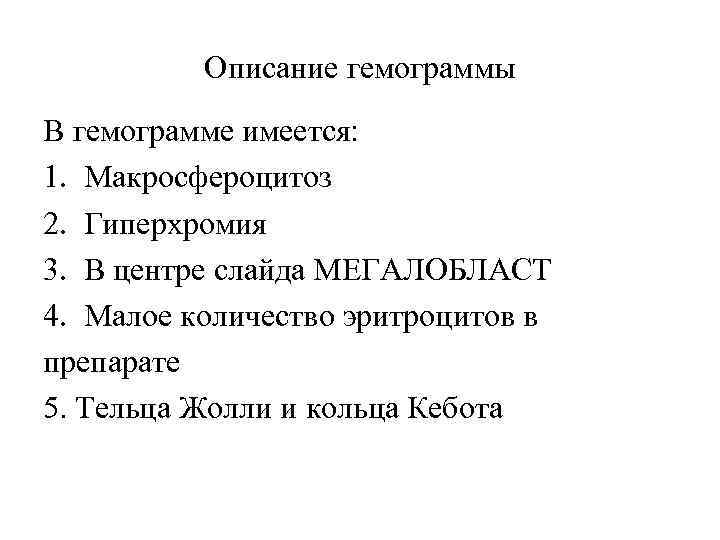

Описание гемограммы В гемограмме имеется: 1. Макросфероцитоз 2. Гиперхромия 3. В центре слайда МЕГАЛОБЛАСТ 4. Малое количество эритроцитов в препарате 5. Тельца Жолли и кольца Кебота

Пример гемограммы при В 12 -дефицитной анемии Эритроциты – 1. 4. 10. 12/л, Нв - 67 г/л, ЦП - 1. 1, Лейкоциты - 4. 10. 9/л, п/я - 2%, с/я - 67%, лимф - 30%, м - 1%, СОЭ 26 мм/час Макроцитоз, отсутствие ретикулоцитов, кольца Кебота, тельца Жоли. Эритроциты – 1. 1. 10. 12/л, Нв - 57 г/л, ЦП - 1. 15, Лейкоциты - 4. 10. 9/л, п/я - 2%, с/я - 67%, лимф - 30%, м - 1%, СОЭ 36 мм/час Макроцитоз, отсутствие ретикулоцитов, кольца Кебота, тельца Жоли,